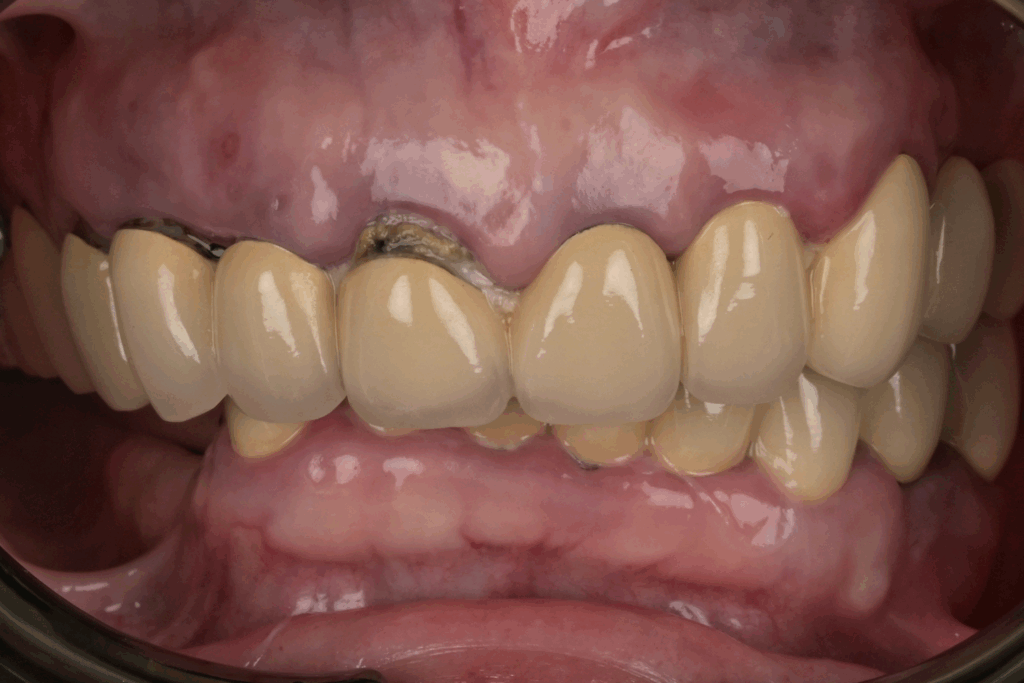

案例1. 上顎+下顎All on X

Before

After